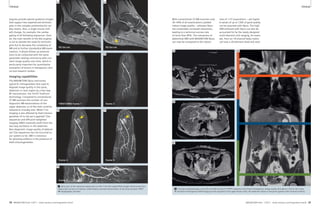

1 2

1 The NYU 7 Tesla scanner. 2 Sagittal image of the ankle of a healthy adult subject.

Note high-resolution depiction of cartilage and trabecular bone.

(Fat-suppressed 3D FLASH, 0.23 x 0.23 x 1 mm3, TR/TE 26/5.1 ms,

60 partitions, acquisition time 6:58 min, custom-designed

transmit-receive extremity coil array with 8 receive elements.)

Ankle

Figure 2 shows a sagittal image of the

ankle obtained at 0.23 x 0.23 mm2

in-plane resolution in a healthy adult

subject using a custom-designed trans-mit-

receive extremity coil array [1]. Note

the high-resolution depiction both of

cartilage and of trabecular bone in this

image. Although no particular pathology

is evident in this example, the ability to

resolve cartilage and bone structure at

this level becomes a powerful asset for

the detection and characterization of dis-ease

processes like those in the examples

to follow.